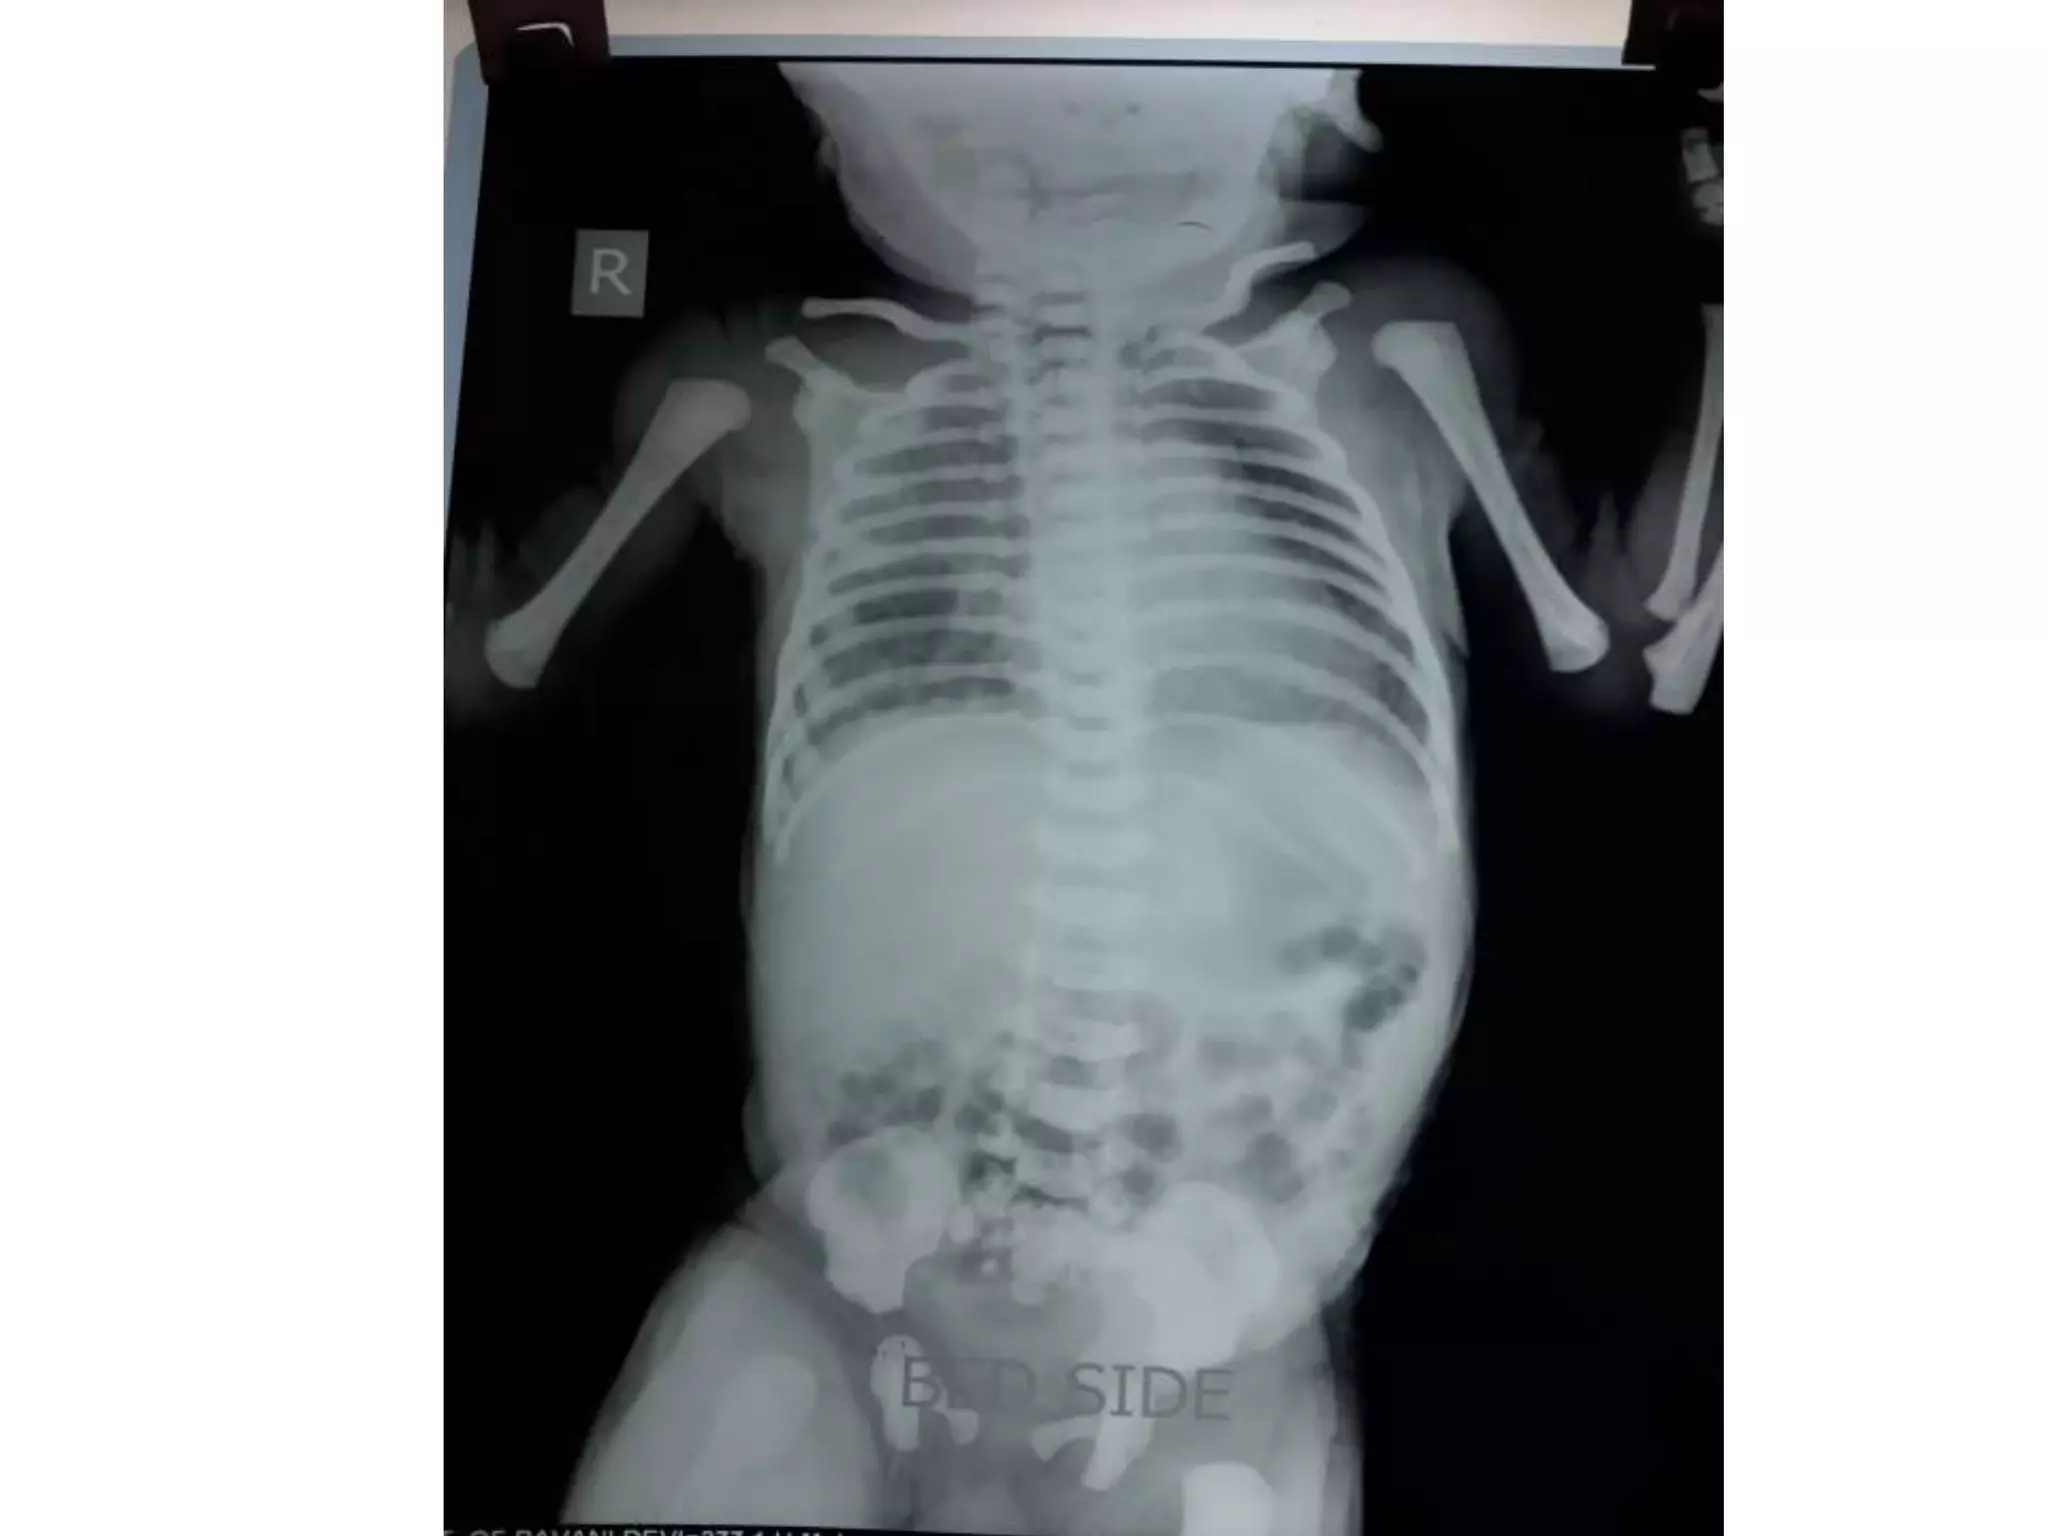

PNEUMOPERITONEUM

Perforated duodenal ulcer .

Perforated peptic ulcer

Bowel obstruction

Ruptured diverticulum

Penetrating trauma

Ruptured inflammatory bowel disease

Necrotising enterocolitis/pneumatosis

coli[1]

Bowel cancer

After laparotomy

After laparoscopy

Breakdown of a surgical anastomosis

Bowel injury after endoscopy

Peritoneal dialysis ]

Vaginal insufflation -water-skiing,oral sex

Colonic or peritoneal infection

From chest (e.g., bronchopleural fistula)

Non-invasive

PNEUMOPERITONEUM Perforated duodenal ulcer. Perforated peptic ulcer Bowel obstruction Ruptured diverticulum Penetrating trauma Ruptured inflammatory bowel disease Necrotising enterocolitis/pneumatosis coli[1] Bowel cancer After laparotomy After laparoscopy Breakdown of a surgical anastomosis Bowel injury after endoscopy Peritoneal dialysis ] Vaginal insufflation -water-skiing,oral sex Colonic or peritoneal infection From chest (e.g., bronchopleural fistula) Non-invasive